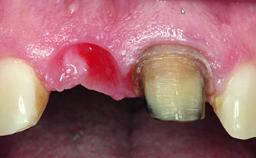

Replacement of a Missing Upper Left Central Incisor: Late Placement of an RC Bone Level Implant, CAD/CAM Zirconia Abutment

A healthy 37-year-old female patient was referred for a consultation on the replacement of missing tooth 21 with an implant-supported restoration. She stated that several years previously the tooth had been traumatically avulsed following a motor vehicle accident. The tooth was replaced with a three-unit fixed partial denture (FPD) immediately afterwards. Over time, she became disillusioned with the FPD and looked for a different option, including orthodontic therapy. She presented still in her orthodontic appliances, with the pontic sectioned free from the FPD but attached to the archwire. Her orthodontist felt that orthodontic treatment had been successfully completed, but nevertheless referred her before removing the appliances in case adjustments were necessary.

| Soft Tissue Contour and Volume | Slightly compromised |